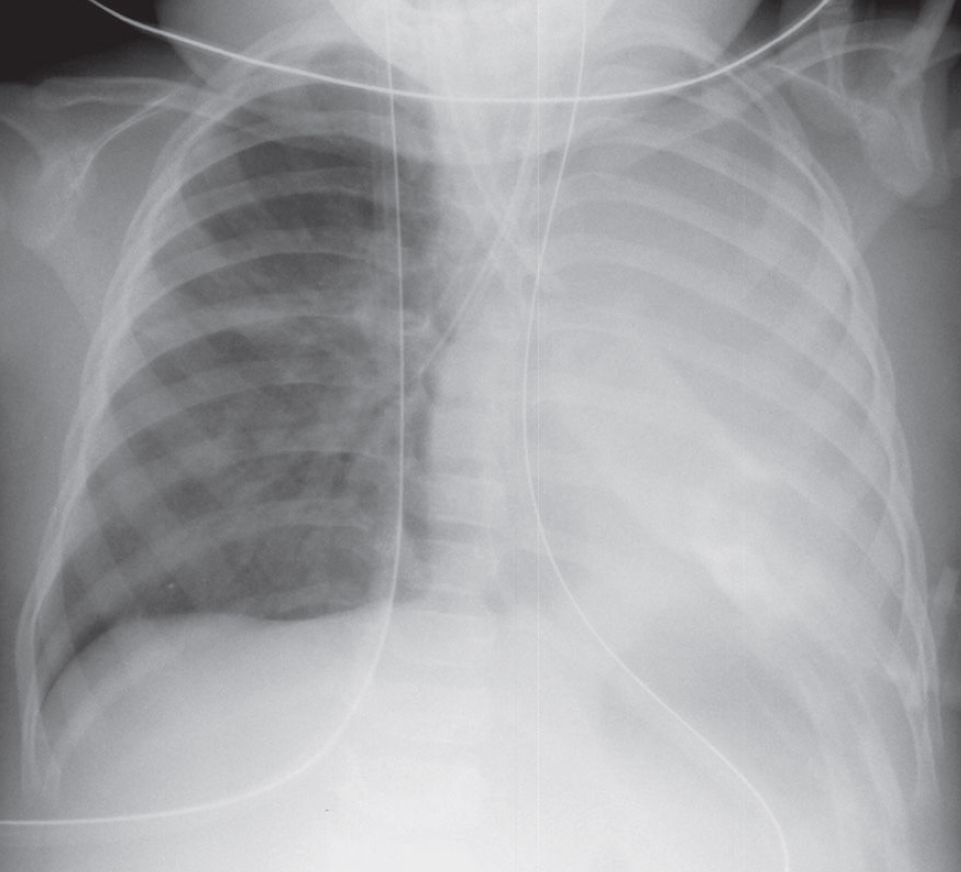

AP chest radiograph demonstrates an opaque left thorax with marked overinflation of the right lung and ipsilateral mediastinal shift. The endotracheal tube is malpositioned, with the tip in the right mainstem bronchus.

Total Atelectasis Left Lung; Inadvertent Right Mainstem Bronchial Intubation

- Opacification of affected thorax

- Ipsilateral mediastinal shift

- Ipsilateral diaphragmatic elevation

- Compensatory overinflation of contralateral lung